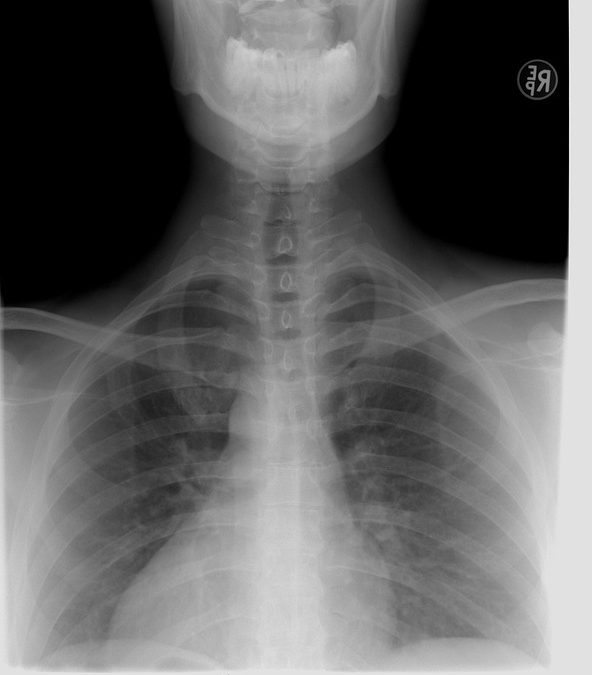

La fecha de este día se tomó de la fecha exacta del descubrimiento de los rayos x por Wilhelm Conrad Roentgen, quién en 1895, realizando un experimento con rayos catódicos y ampollas de vidrio al vacío, notó que cuando la corriente atravesaba la ampolla, se producía un efecto fluorescente, algo que también ocurría sobre la placas fotográficas. Este científico llamó a su descubrimiento rayos x.

Tiempo después Roentgen informó al gremio científico y médico, que con estos rayos podía ver el interior del cuerpo de una persona y a los 3 meses de su descubrimiento, ya se estaban reproduciendo radiografías en los hospitales de las grandes ciudades.

Gracias a la radiología hoy en día se pueden curar fracturas, poner prótesis adecuadas a cada situación, observar la evolución y desarrollo de los fetos y poder conocer la condición real de un cerebro. Y todo esto, sin tener que someter a una persona a cirugía u otro tipo de intervenciones dolorosas.